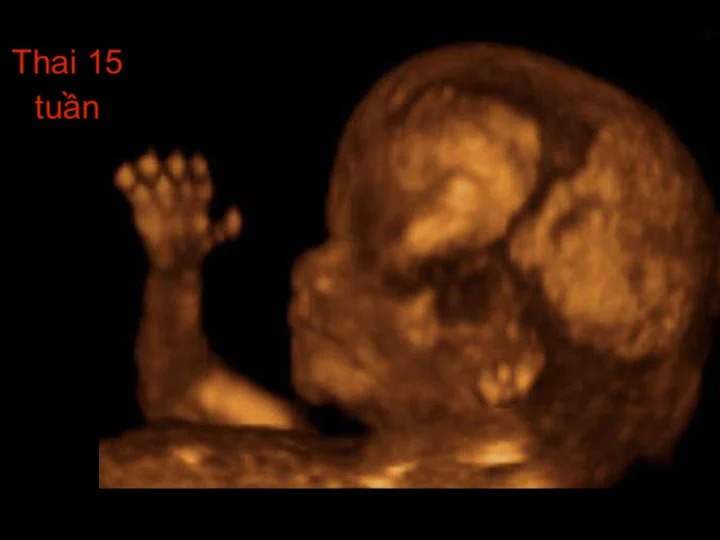

Khi bước sang tuần mang thai thứ 15, có lẽ cảm giác hồi hộp, háo hức, lo âu... ban đầu của các bà mẹ sẽ không còn nữa. Đây là mốc thời gian quan trọng, các mẹ cần hết sức lưu ý bảo vệ sức khỏe để tạo tiền đề phát triển tốt nhất cho thai nhi. Lúc này, hệ thống xương khớp dần được hoàn thiện, các khớp ngón tay, ngón chân dài ra giúp cơ thể thai nhi vận động dễ dàng.

Tuy nhiên, những cử động này xuất hiện với tần suất khá nhỏ do thai nhi 15 tuần tuổi chưa phát triển nhiều về kích cỡ cơ thể, thai 15 tuần chỉ dài vỏn vẹn 16,7cm và nặng 117g tương đương với một quả chuối.

Các cơ quan thần kinh phát triển, đặc biệt là các xung thần kinh trí não giúp hình thành cảm xúc và nhận thức của thai nhi. Quá trình tổng hợp protein diễn ra khá mạnh mẽ trong giai đoạn mang thai 15 tuần, hỗ trợ phát triển da, tóc và móng cho thai nhi.

Ngoài ra, khá nhiều người thắc mắc thai 15 tuần biết trai hay gái chưa? Khi thực hiện siêu âm, hình ảnh thai 15 tuần có khả năng cho biết giới tính bởi lúc này cơ quan sinh dục của bé đã được hình thành. Tuy vậy, độ chính xác giới tính ở thời điểm này chưa cao, nhất là khi bé nằm ở tư thế không thuận lợi hoặc bác sĩ chưa có nhiều kinh nghiệm. Mẹ bầu vẫn nên siêu âm thêm ở các tuần sau để biết giới tính của bé chính xác hơn.